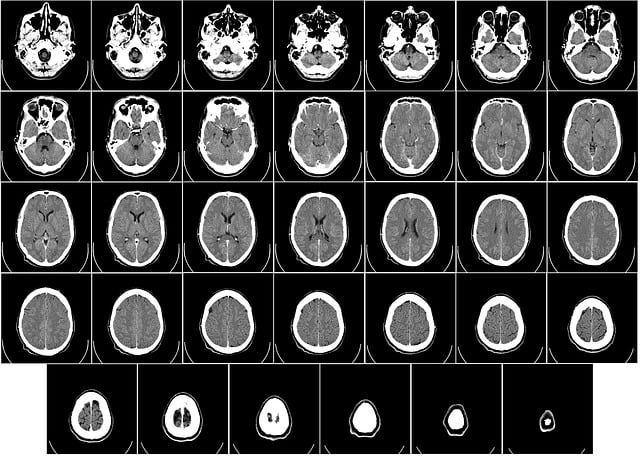

네 세번째 단계까지 오셨다면 높은 확률로 치매일 수 있습니다. 이 검사는 두번째 치매진단검사에서 치매로 진단이 나오면 받아야하는 검사입니다. 병원에서 진행하며 씨티와 엠알아이를 이용하여 뇌영상을 촬영하게됩니다. 엠알아이가 정확도는 높으며 비용은 비싼 편입니다.

씨티 검사의 경우 6~8만원정도 하며, 엠알아이는 20~30만원입니다. 두 검사 모두 이전에 비하여 비용부담이 많이 줄어든 편입니다.